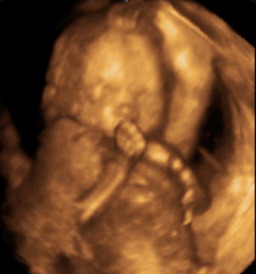

Csipetnyusza: drukk Neked az UH-ra!

Freyja: Neked is megy a drukkkkkkk!

Maki: és Neked is megy a sok-sok drukkk!